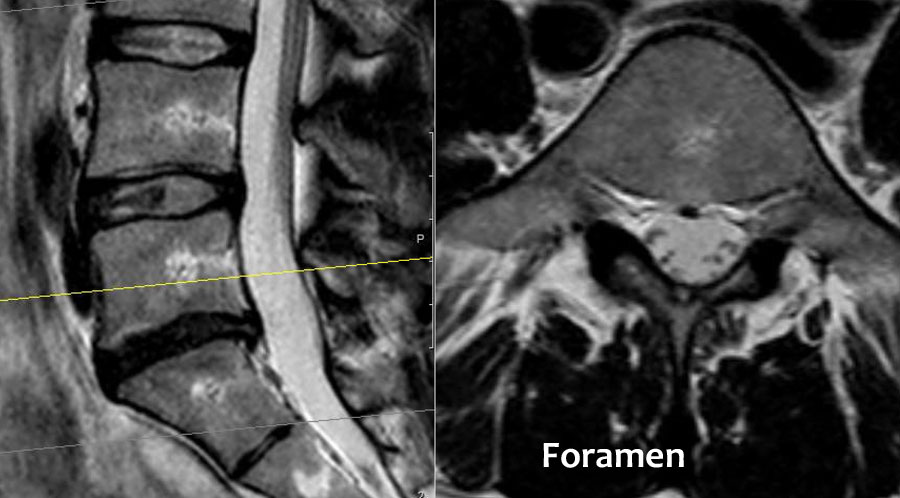

Cuộn qua các hình ảnh để quan sát đường đi của các rễ thần kinh tại mức độ đĩa đệm, ngách bên, lỗ liên hợp và ngoài lỗ liên hợp.

Tại mỗi mức độ có thể thấy các bệnh lý đặc trưng, nhưng có sự chồng lấp đáng kể.

Ví dụ, đĩa đệm có thể thoát vị và gây chèn ép thần kinh tại mức độ đĩa đệm, nhưng cũng có thể di trú xuống tầng thấp hơn và chèn ép rễ thần kinh trong ngách bên, hoặc di chuyển lên trên và gây chèn ép tại mức độ lỗ liên hợp hay ngoài lỗ liên hợp.

Hẹp ngách bên được gây ra bởi thoái hóa khớp mỏm khớp, thường kết hợp với phì đại dây chằng vàng và phồng đĩa đệm. - Lỗ liên hợp.

Đây là vùng nằm giữa hai cuống sống, nơi rễ thần kinh thoát ra khỏi ống sống.

Hẹp lỗ liên hợp được gặp trong thoái hóa khớp mỏm khớp, trượt đốt sống và thoát vị đĩa đệm trong lỗ liên hợp – thường là đĩa đệm di trú từ tầng thấp hơn. - Ngoài lỗ liên hợp.

Đây là vùng nằm bên ngoài lỗ liên hợp.

Chèn ép thần kinh tại vùng này không phổ biến, nhưng đôi khi do thoát vị đĩa đệm sang bên gây ra.